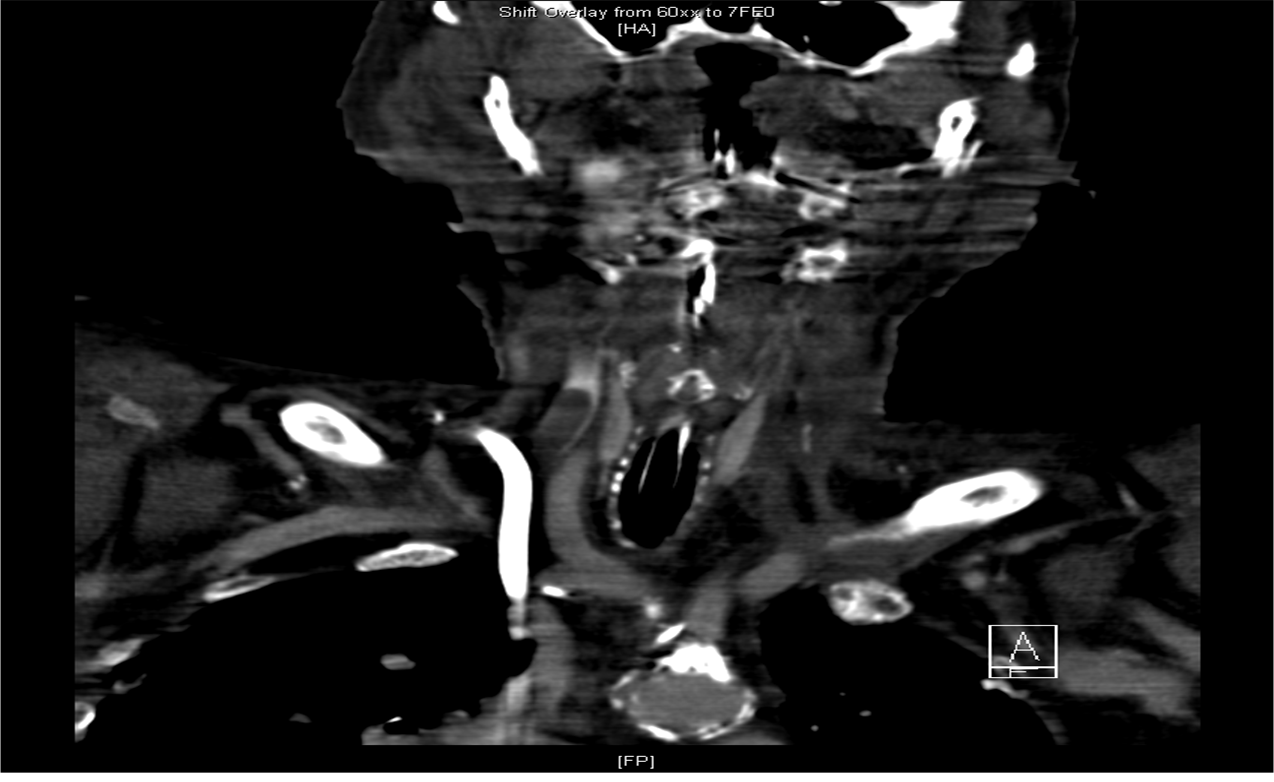

The following day she presented to the ED with dyspnea, tongue and facial swelling. A laryngoscope found laryngeal swelling and she was intubated emergently. She had a CT neck which is shown below:

She previously had received radiotherapy to her neck for a SCC of unknown origin which had left her with no jugular vein on the left and chronic supraglottic edema. Shortly after insertion of the line, a clot formed in her RIJ proximal to the catheter which, in the absence of a LIJ led to a SVC-like syndrome. She was treated with intravenous heparin and eventually removal of the catheter.